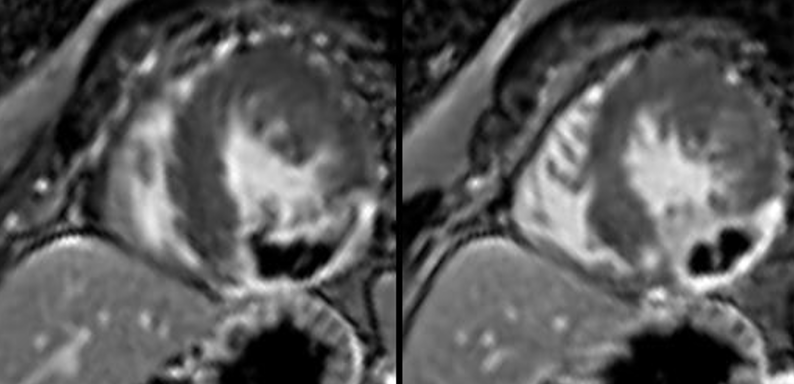

HCM or MINOCA?

Transmural LGE with presence of MVO